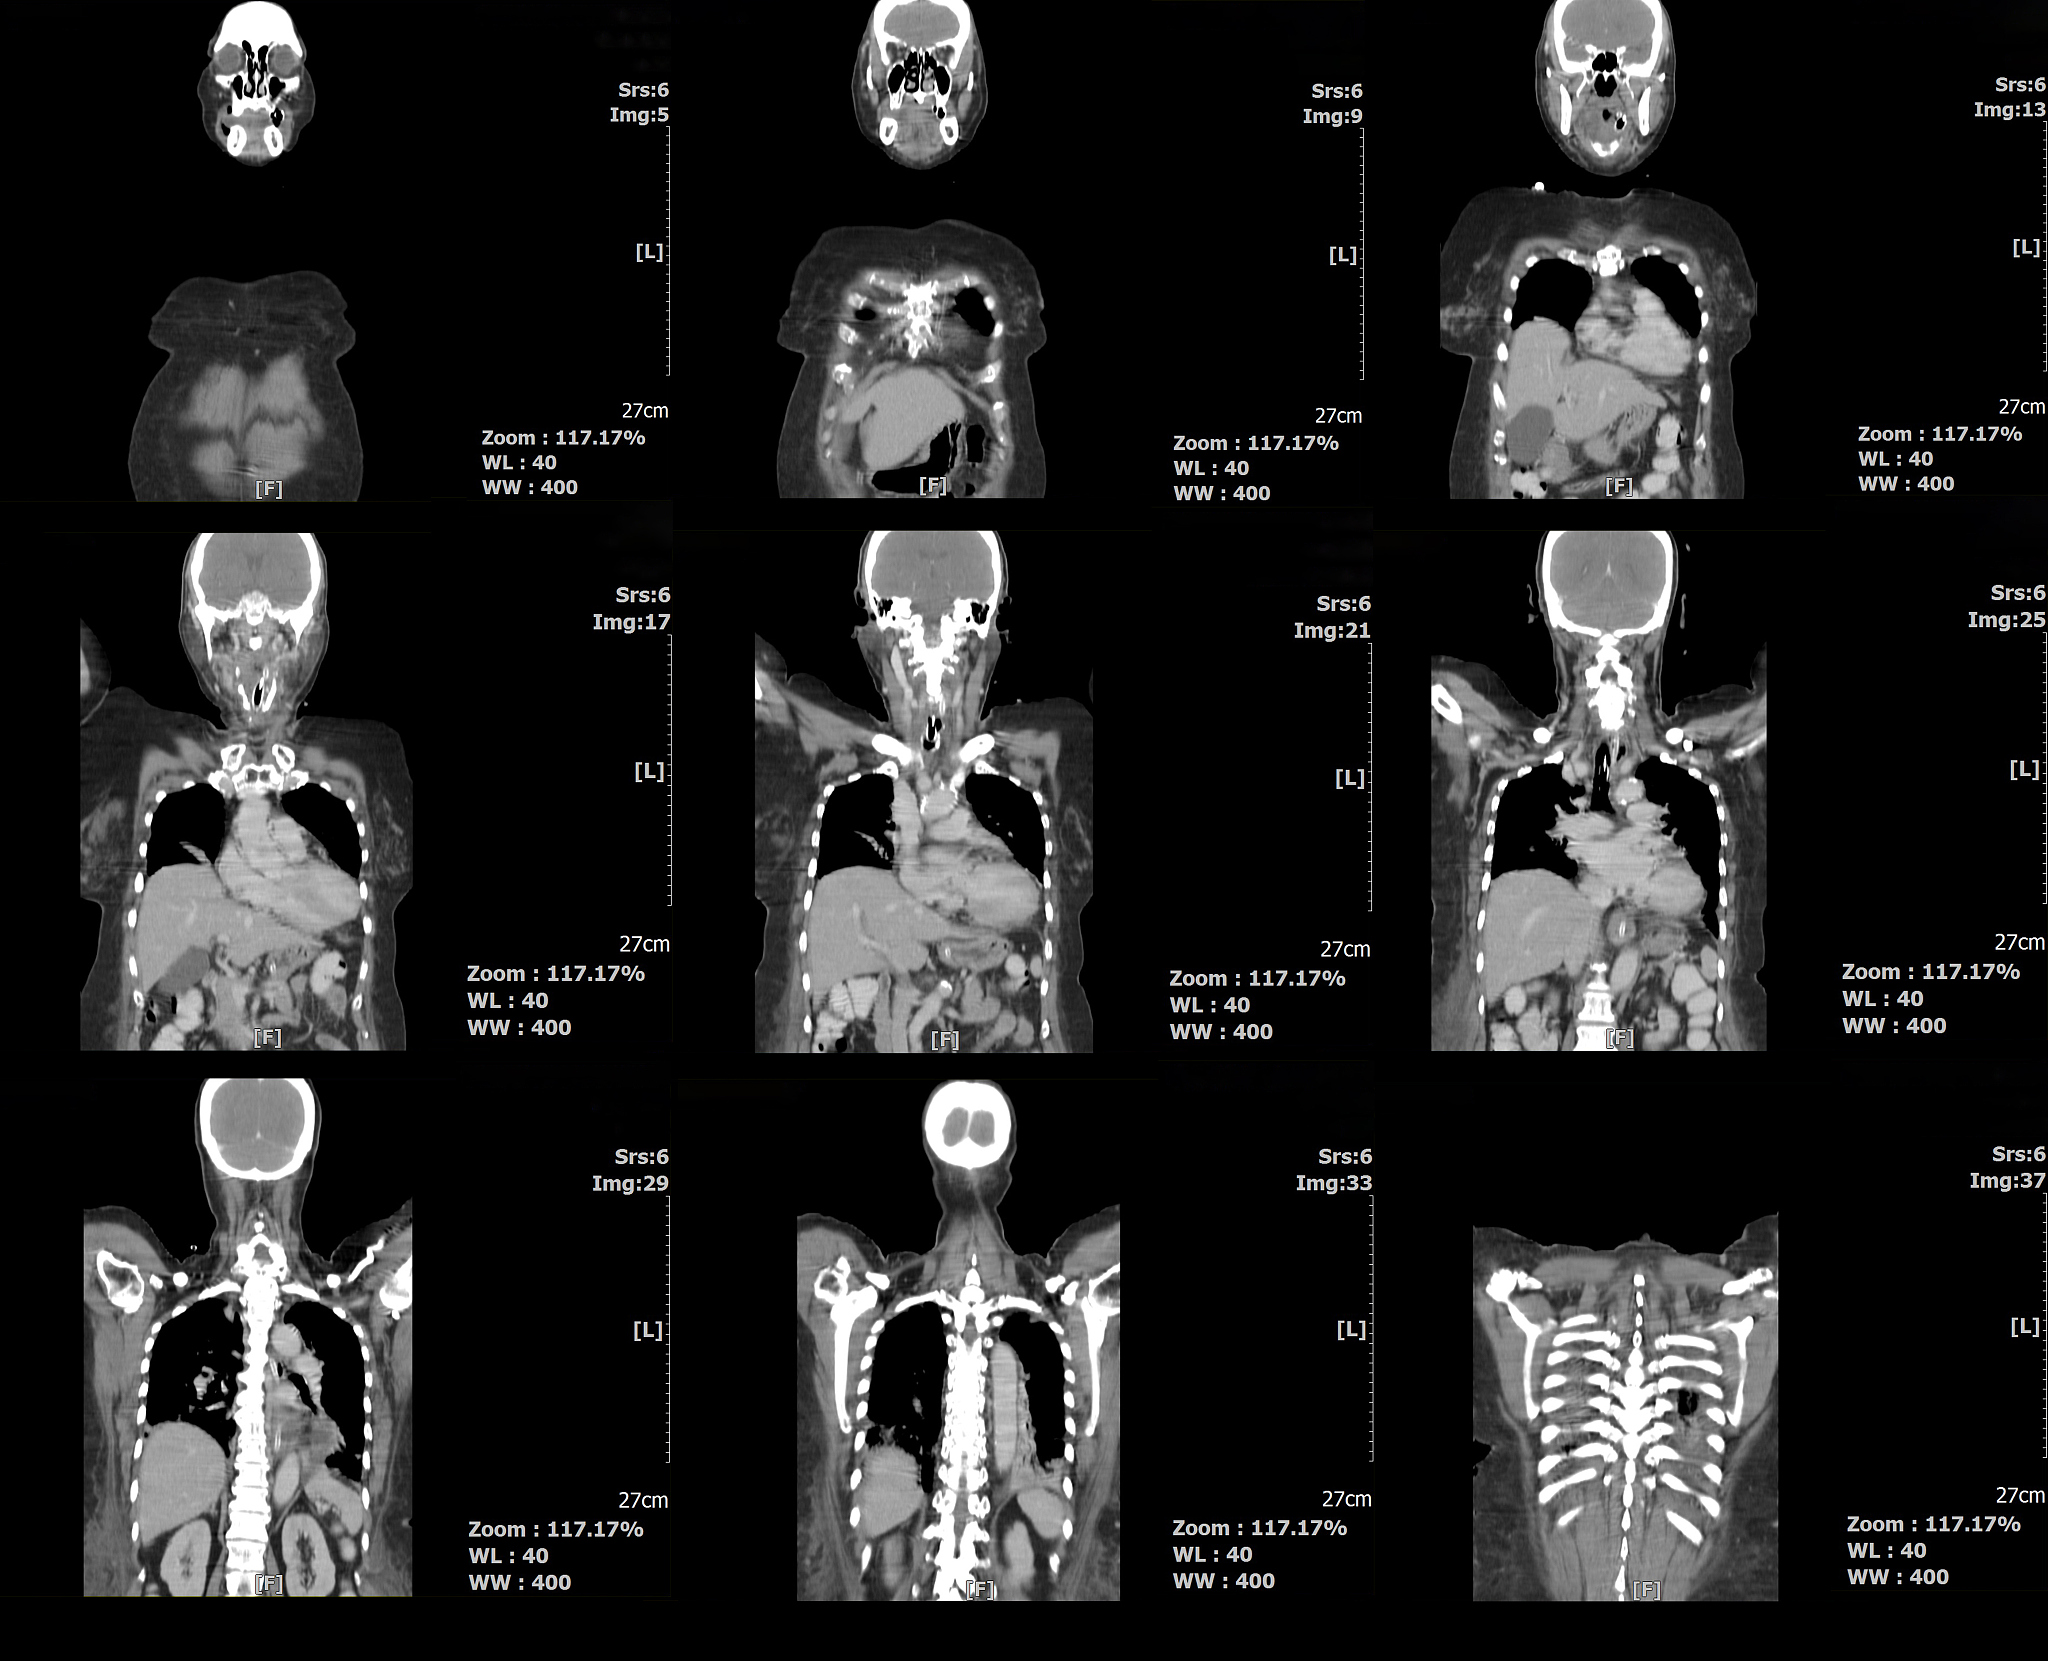

Objective: The objective of this study is to explore and summarize the technical features and clinical efficacy of Dyna-computed tomography (CT)-assisted neuroendoscopic hematoma evacuation for treating hypertensive intracerebral hemorrhage (HICH).

Dyna-CT Assisted Neuroendoscopic Hematoma Evacuation for Hypertensive Intracerebral Hemorrhage: A Review